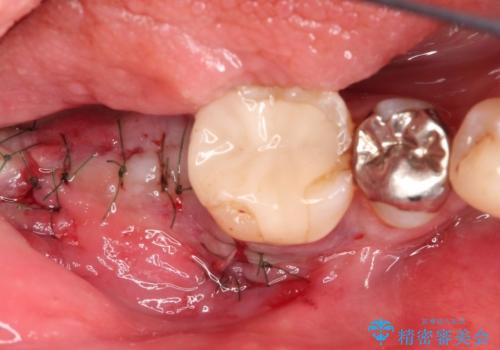

抜歯後十分な骨の回復が認められず、単独の骨増生を行った後にインプラントを埋入しました。

インプラント埋入時に骨が足りない場合にはインプラント埋入前に骨増生を行います。また、インプラント周囲の角化歯肉が不足した場合は角化歯肉の移植も行うことがあります。

どちらの治療もインプラントの長期予後を高めるために必要な治療です。